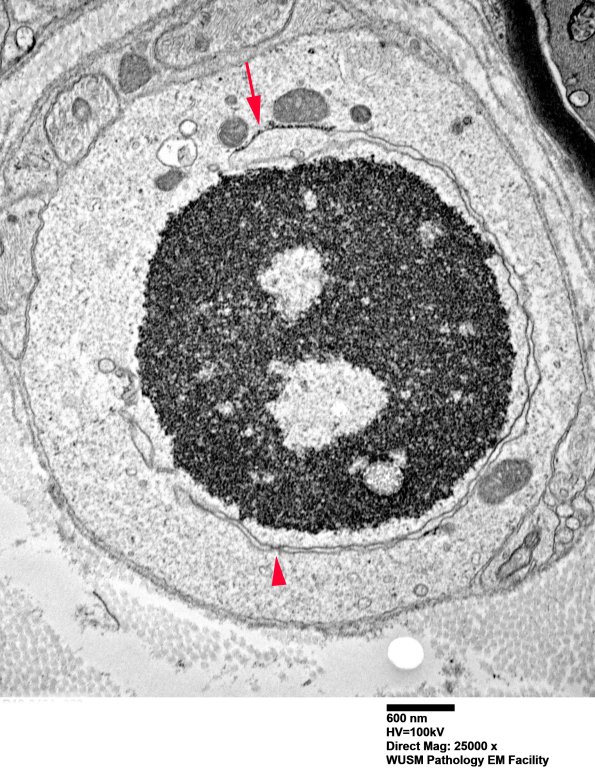

We have considered a variety of entities but tentatively thought these were degenerating Schwann cell nuclei. (electron micrograph)